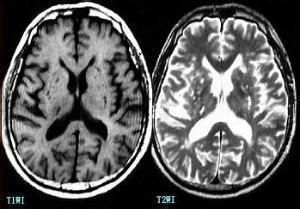

3、頭顱CT在病後8~11天檢查較適宜。

4、MRI對腦幹腔隙梗塞亦清晰可見。

2.顱腦CT檢查是腔隙性腦梗塞診斷中重要的檢查,其可對梗塞部位、數量、範圍作出準確判斷。顱腦核磁共振成像(MRI)檢查,其可更早、更為準確的顯示腔隙梗塞病源。